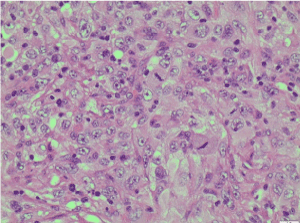

Histological features and immunoprofile of metastatic high grade sarcomatous renal carcinoma of left supraclavicular lymph node were depicted in Figures 4-11.

Figure 6. H&E X400 [Haematoxylin and Eosin stain X400]. Tumour cells show pleomorphic nuclei, prominent nucleoli and frequent mitoses